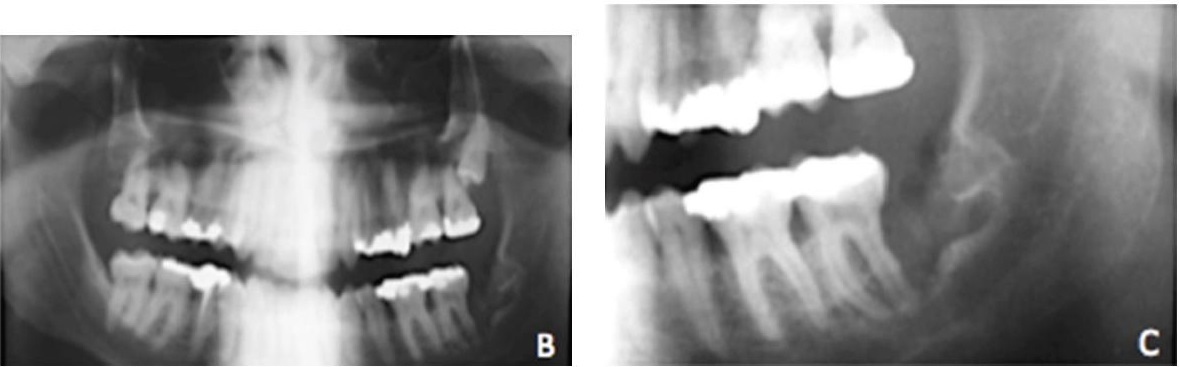

Удаление зуба с кистой: фото до и после